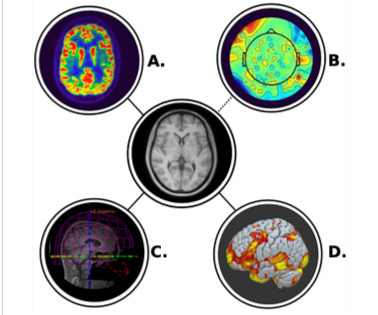

CAPSI rekrytera patienter med en pågående vårdkontakt vid onkologklinik i Region Stockholm, Uppsala, Västra Götaland eller Örebro. Totalt lottas 100 patienter med cancer och depression till behandling med psilocybin eller placebo. Studien undersöker antidepressiv effekt, liksom potentiella biverkningar sex veckor och sex månader efter dosering. Dessutom studeras bland annat olika aspekter av den terapeutiska komponenten samt det hälsoekonomiska värdet av behandlingen. Samtliga patienter lämnar blodprov och genomgår EEG undersökning före och efter behandlingen. De 50 patienter som deltar i Region Stockholm och Uppsala undersöks dessutom med tre andra metoder (MEG, fMRI och PET) . Dessa data ska dels användas för att förstå psilocybins verkningsmekanism vid depression, dels för att utveckla ett prognosverktyg för att identifiera de patienter som skulle kunna ha hjälp av psilocybinbehandling.